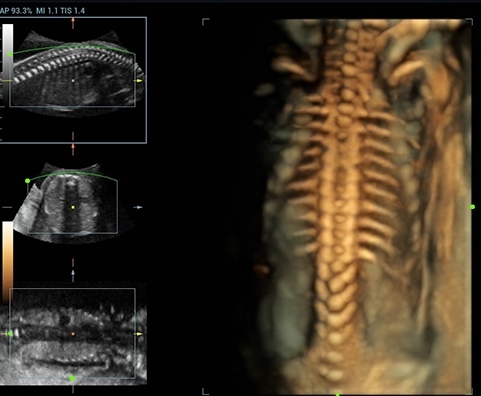

• Инновационная технология ZONE Sonography™: Эта передовая технология значительно улучшает качество изображений, предоставляя сверхчеткие и детализированные визуализации анатомических элементов, что крайне важно для решения сложных диагностических задач;

• Широкий частотный диапазон до 20 МГц: Устройство позволяет проводить исследования на высоких частотах, обеспечивая вопиющую четкость изображений и улучшенную видимость мелких сосудов и структур;

• 4D Function — модуль объемного сканирования;

Изображения